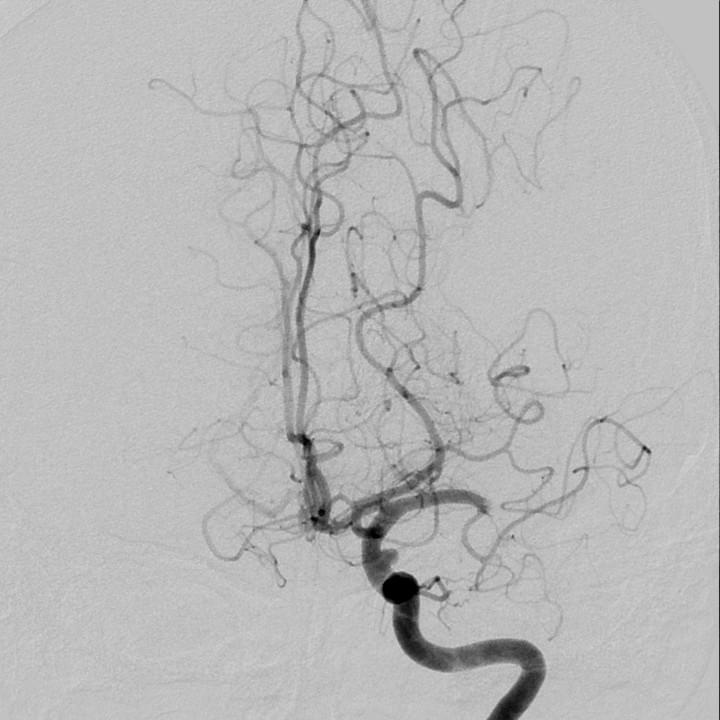

Distinct intra-arterial clot localization affects tissue-level collaterals and venous outflow profiles

Faizy TD, et al. (2021) European Journal of Neurology. Dec;28(12):4109-4116. doi: 10.1111/ene.15079. Epub 2021 Aug 30.

Association of Venous Outflow Profiles and Successful Reperfusion After Thrombectomy

Faizy TD, et al. (2021) Neurology May 5;10.1212/WNL.0000000000012106.

doi: 10.1212/WNL.0000000000012106

Favorable Venous Outflow Profiles Correlate With Favorable Tissue-Level Collaterals and Clinical Outcome

Faizy T, et al. (2021) Stroke Mar 8;STROKEAHA120032242.

doi: 10.1161/STROKEAHA.120.032242.Online ahead of print.